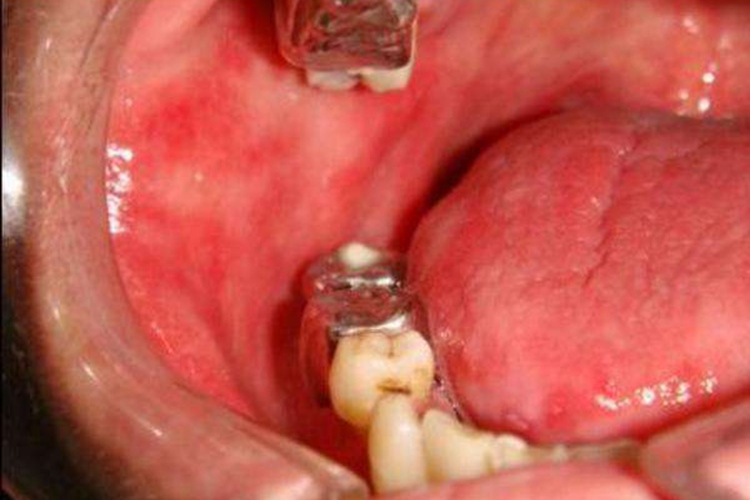

慢性红斑型念珠菌病:此型又称为义齿性口炎,因其多发生于戴义齿的患者。临床表现为义齿的承托区黏膜广泛发红,形成鲜红色、界限弥散的红斑,可见红斑表面有颗粒形成。